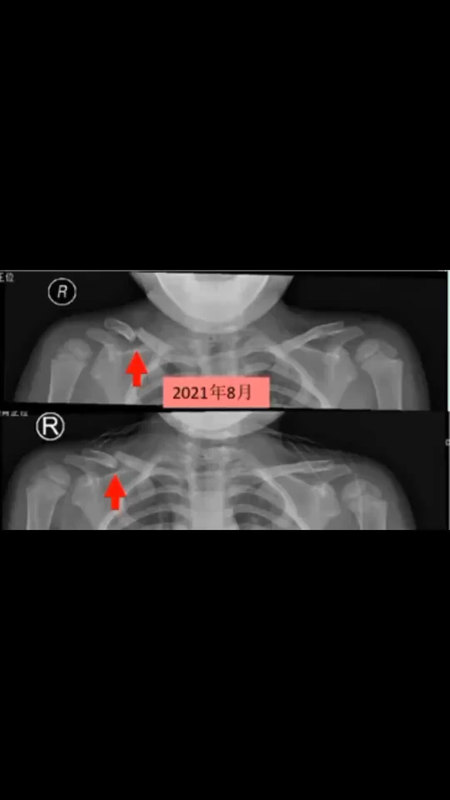

三岁孩子锁骨骨折保守治疗骨折愈合及塑型过程

吴德超医生的科普号

2023年06月13日